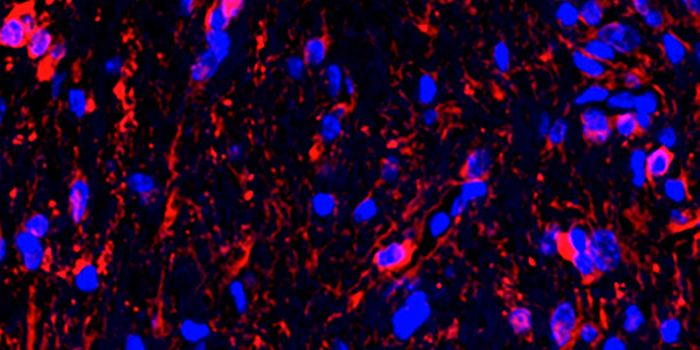

NOV 03, 2021Genetics & GenomicsIn Parkinson's disease, neurons that produce the neurotransmitter dopamine in a part of the brain called the substantial ...